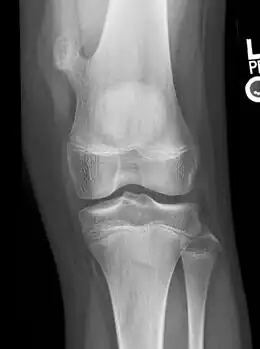

![]() | |

| X-ray knee (side view): ossification in the peritendinous tissues in a person with osteochondroma. | |